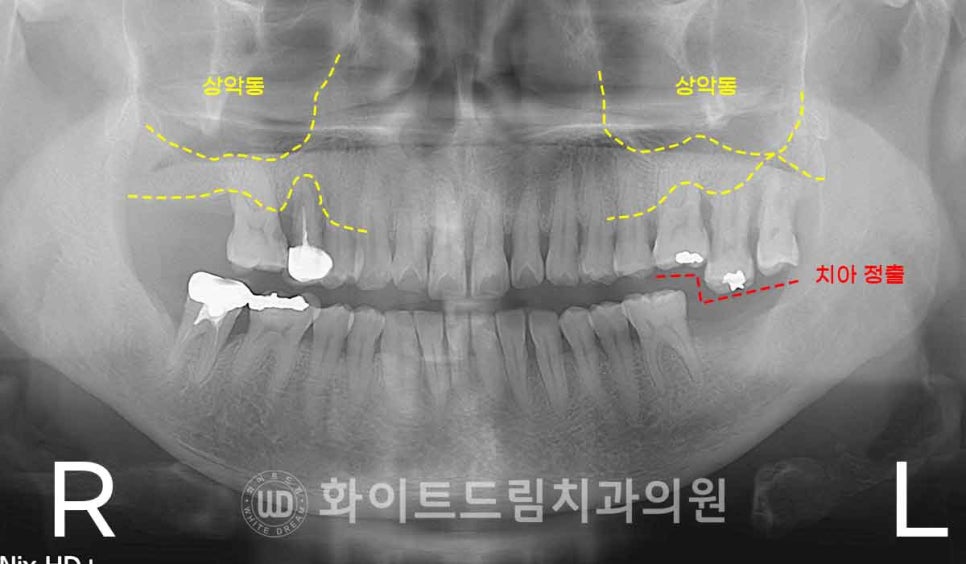

환자분의 초진 x-ray 사진부터 보겠습니다.

양측 어금니 부위의 치아들은

뿌리 주변으로 치주염과 골흡수가 상당히 진행된 모습을 보이고 있었습니다.

치근을 잡아주는 잇몸뼈가 많이 녹아 있어 지지력이 거의 없었고,

왼쪽 상악 어금니 치아는 하악 어금니 치아의 상실로

치아가 하방으로 내려오는 정출까지 나타나면서

더 이상 보존이 어려운 상태였죠.